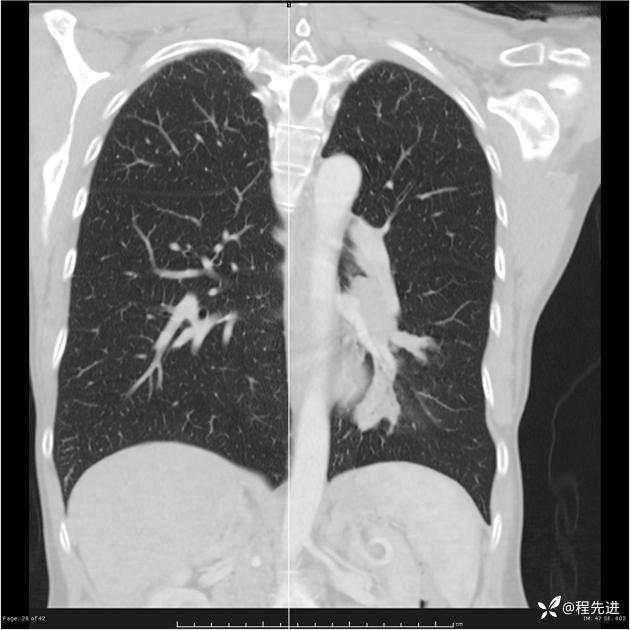

病例女,53岁,气管、左主支气管、下叶支气管内结节,乳头状瘤?期待你的精彩解读

女,53岁

乳头状瘤?